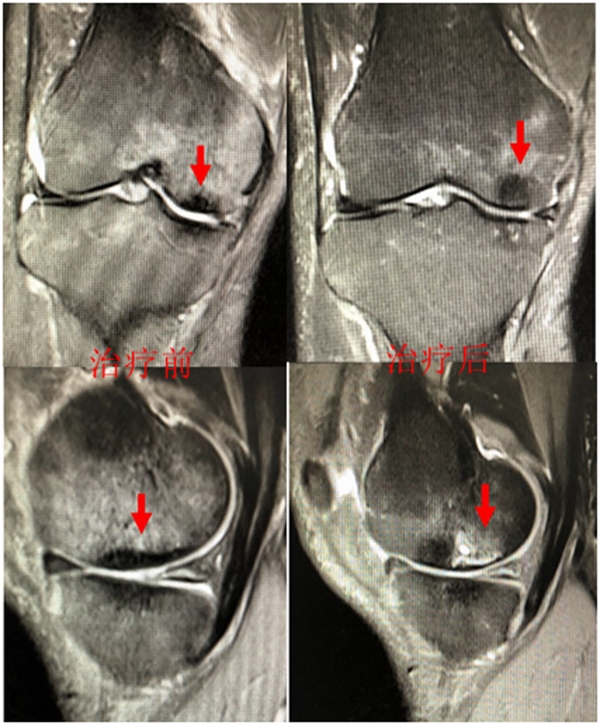

病例1:女,65岁,主诉右膝关节内侧疼痛1周。2018年1月X光未见右膝骨质异常,MR检查见股骨内侧髁骨坏死,半月板相对突出百分比(RPE)28.99%,关节线会聚角1.4°。

予切开行克氏针钻孔减压,口服消炎止痛药物、钙剂及骨化三醇,不负重6周,后改部分负重至3个月。2018年4月复查MR见骨髓水肿基本完全吸收,坏死区局限并修复良好,半月板相对突出百分比(RPE)32.08%,患者临床症状消失。